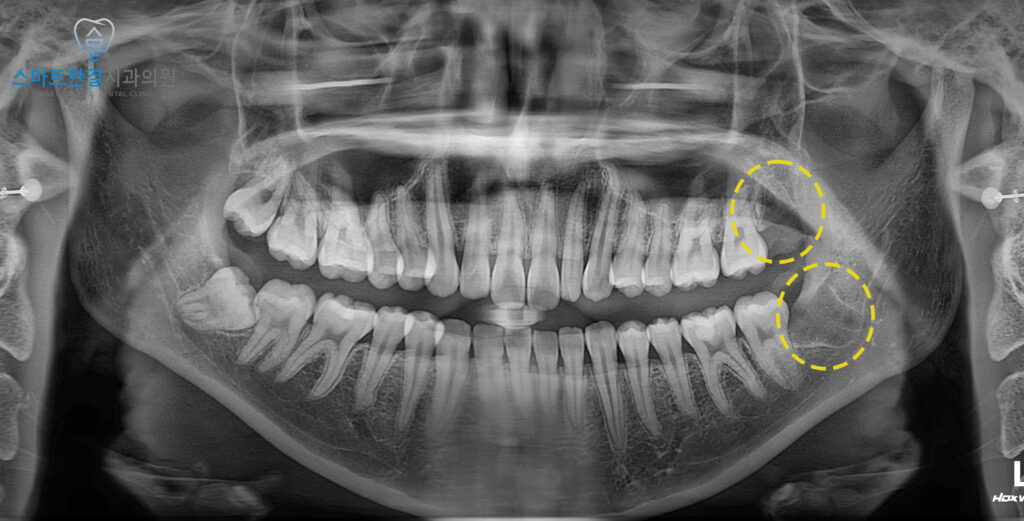

<수술적으로 사랑니 발치>

왼쪽 위, 아래 2개의

사랑니를 발치한 모습이에요.

또한, 사랑니의 뿌리와 신경관이

파노라마 사진에서 중첩되어 확인되어,

발치 전 3D CT 촬영을 통해 정밀하게 분석한 후

안정적으로 발치를 진행하였답니다. (^^)